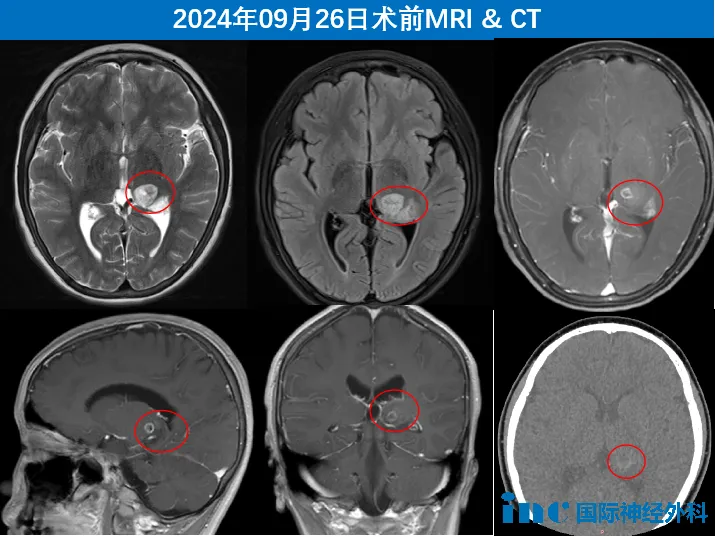

这是一名年仅10岁的左侧丘脑占位性病变患儿

肿瘤呈弥漫性生长迹象,侵入脑实质。从两个月前开始,佑佑就觉得身体麻麻的,左手和左脚也没右边那么有劲儿。面对着一个无法排除高级别可能性的肿瘤,采取迅速而果断的手术干预有着重要意义。迟疑与观望,都无异于将这一棘手的问题深埋于时间的土壤中,任其悄无声息地滋生蔓延,这不仅会错失治疗的黄金时机,更可能让那潜藏的肿瘤如野草般在佑佑稚嫩的大脑中肆虐,带来不可逆转的伤害。